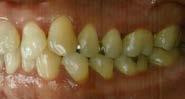

Estudio de caso

El paciente se presentó después de varios años de sufrir una herida traumática en sus dientes anterio res superiores. Las piezas 11 y 21 tenían varias fracturas, así como el borde incisal de la pieza 12. Por lo que él deseaba mejorar su estética bucal, y yo quería asegurarme de restaurar la funcionalidad y resisten cia también. El paciente necesitaba completar su tratamiento en un cor to periodo de tiempo, por ello debí realizar ajustes en mi flujo de traba jo. (Figura 1).

Cita 1. Impresiones iniciales y planeación del tratamiento

Mi plan era restaurar los dientes 12-22 con carillas BruxZir® Esthe tic, así que tomé un escaneo digital de ambas arcadas completas, ade más del registro de mordida usan do el escáner iTero® Element (Align Technology; San Jose, Calif.). Puede tomar impresiones de vinil polisiloxa no (VPS) si lo prefiere, pero el esca neo digital reduce tiempos al eliminar la necesidad de enviar modelos físicos o impresiones al laboratorio. Envío dicho escaneo junto con instruccio nes específicas para que Glidewell fabrique un encerado de diagnóstico (Figura 2).